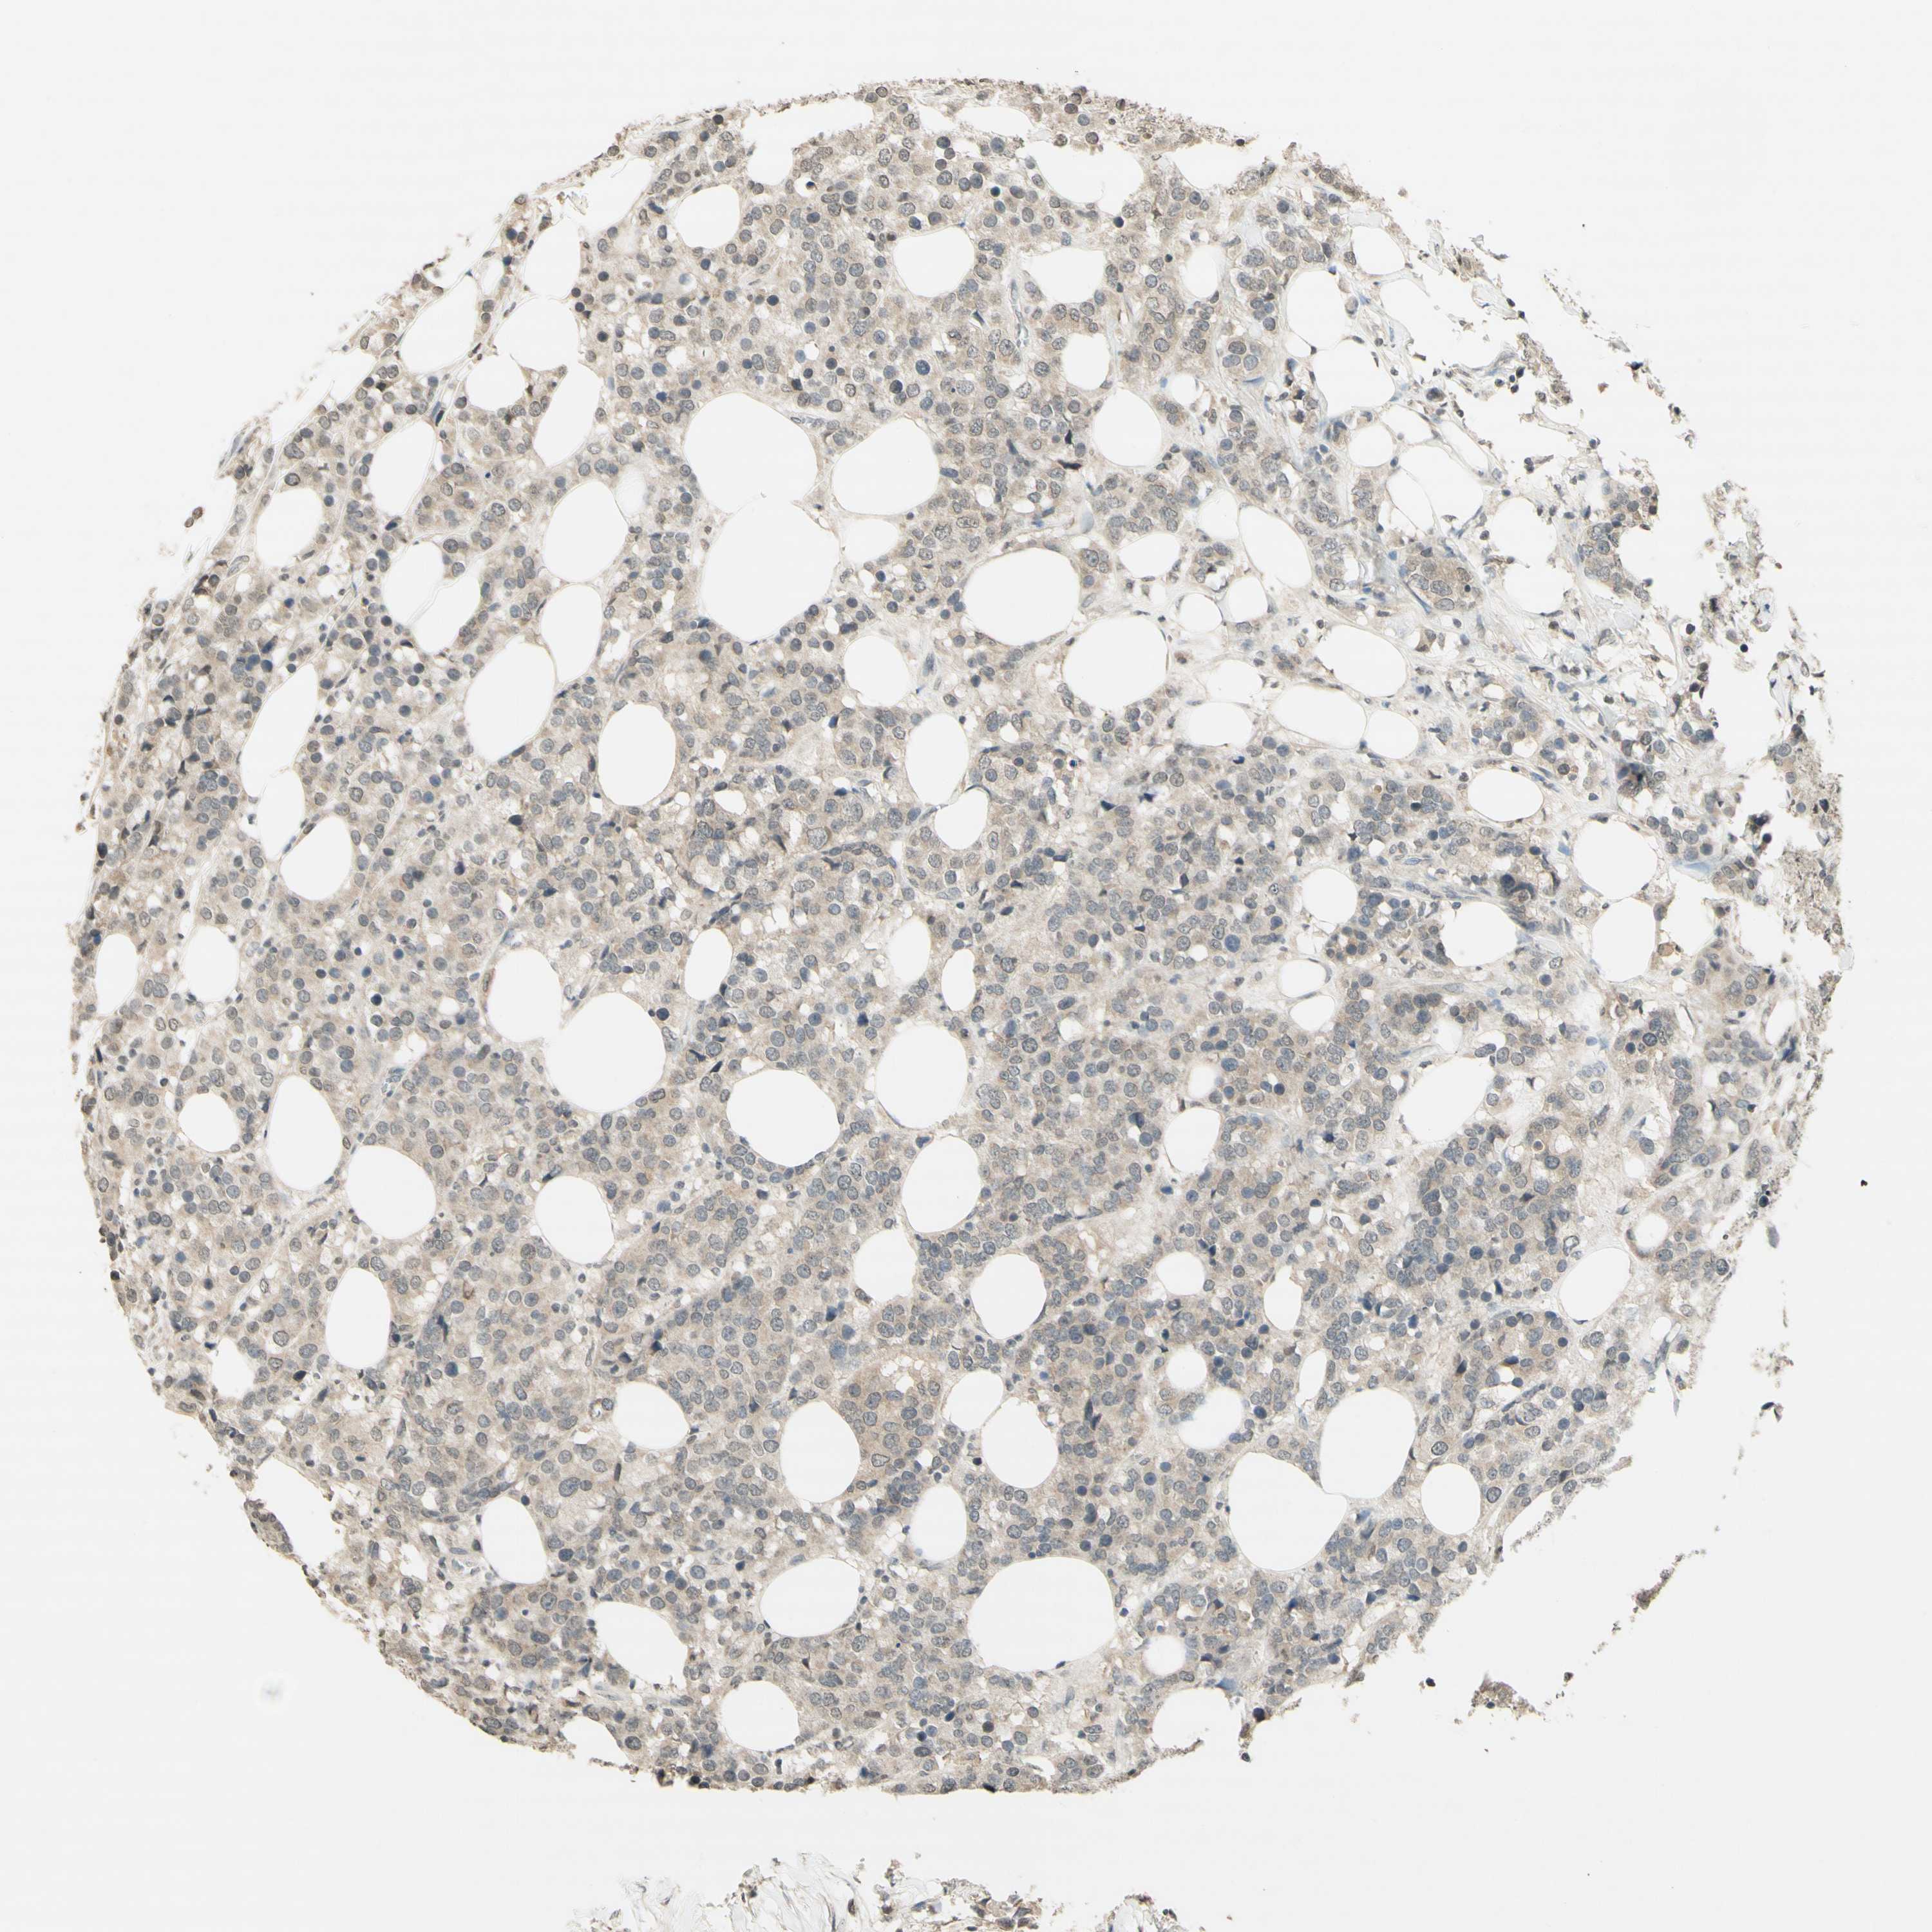

CANCER BREAST CANCER Show tissue menu

BRCA TCGA BRCA VALIDATION PROTEIN EXPRESSION

ANTIBODIES

AND

VALIDATION